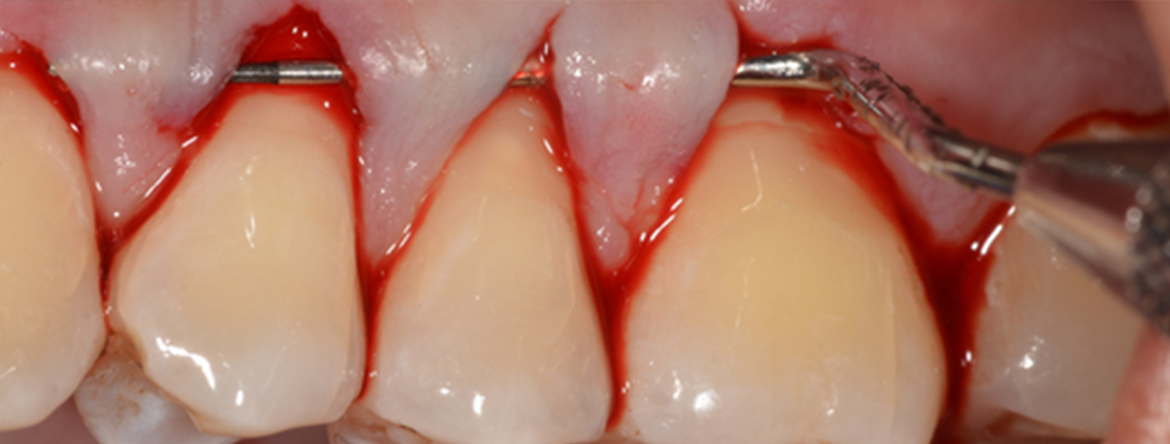

- Descrição da técnica para aumento de banda de gengiva queratinizada (enxerto gengival livre) e de recobrimento radicular (enxerto de tecido conjuntivo): Fatores a considerar, indicações clínicas, técnicas e discussão de casos clínicos.

- Indicações da cirurgia para recobrimento radicular de recessões múltiplas (retalho de reposicionamento coronal modificado e técnica em túnel).

- Técnicas cirúrgicas “passo a passo” com recurso a casos clínicos.

Fotos dos casos clínicos